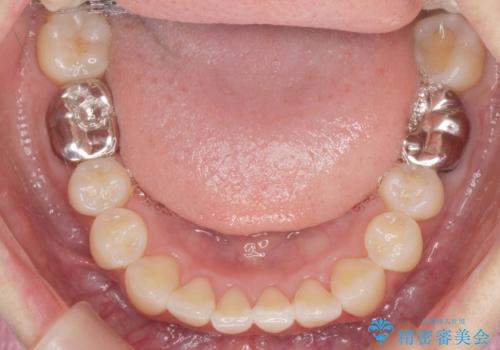

- 矯正装置

- インビザライン +部分ワイヤー矯正

マウスピース矯正システムインビザラインで歯の後方移動、咬合関係の修正を行ったのち、引っ込んでいる左上2をワイヤーを用いて短時間で引き出す治療計画としました。

部分ワイヤー矯正を行なったことで約3ヶ月という短期間で前歯を綺麗に並べることができました。